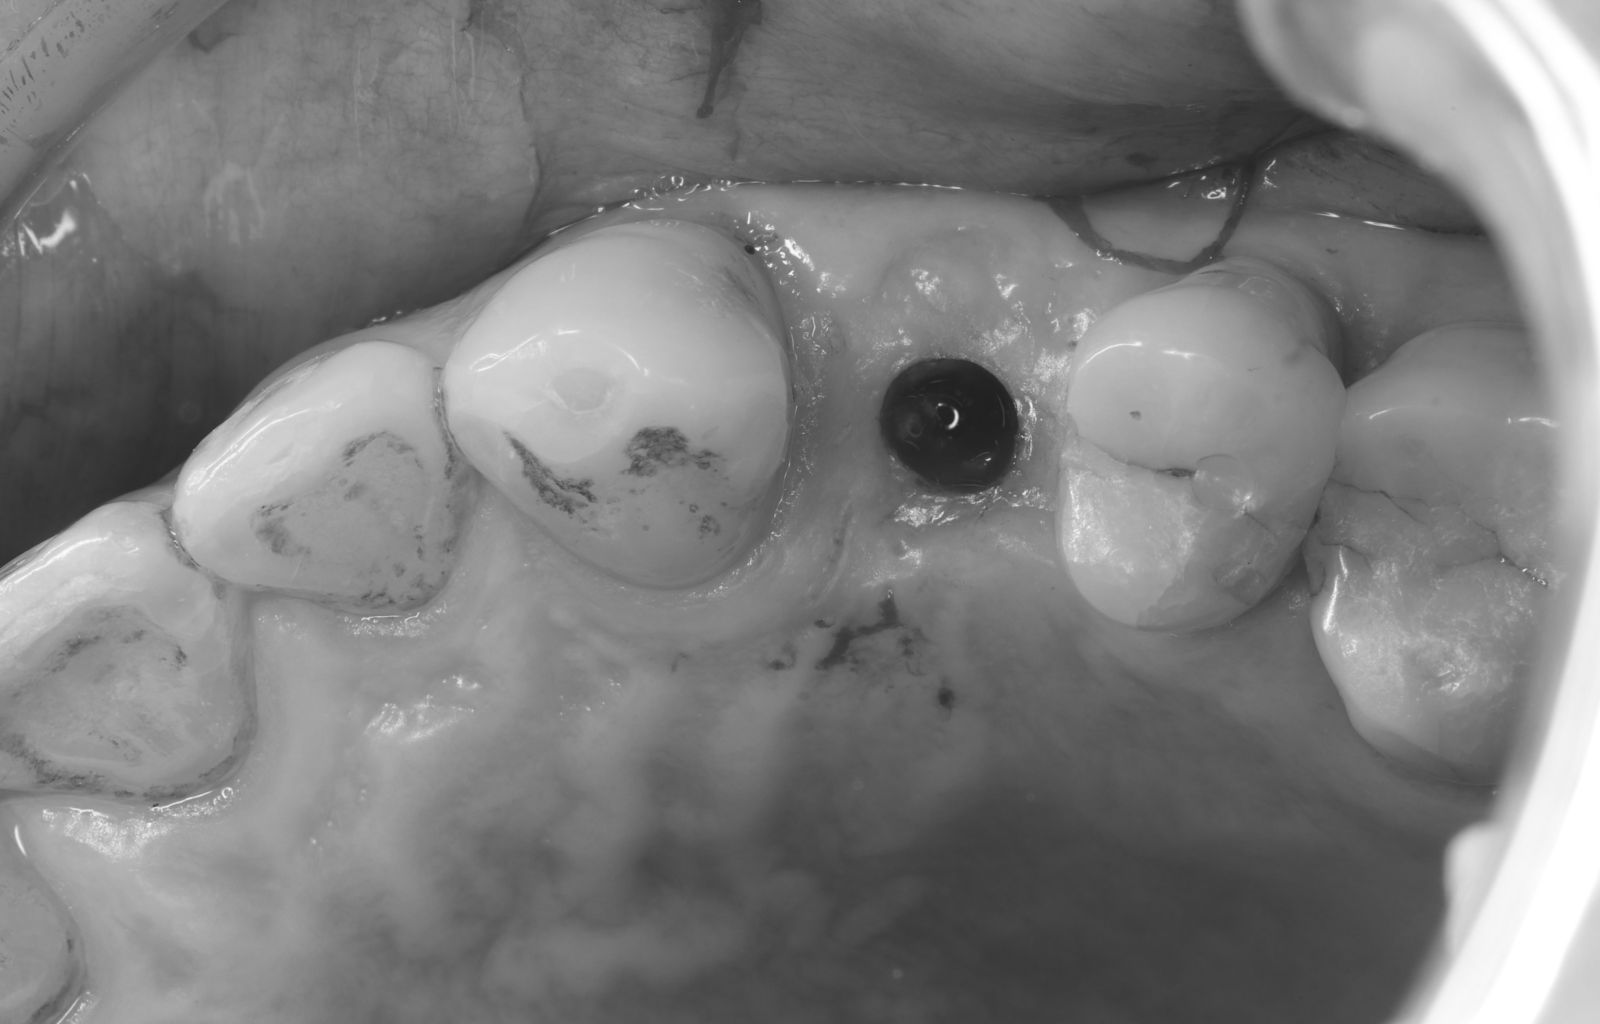

【 案 例 一 】

- 手術過程,在植入植體前先用導板定位,確認植牙位置及角度。

- 植牙當下不用劃開傷口無須縫合,鎖上癒合帽即可,也不需縫合傷口

待3.4個月後裝上全陶瓷牙冠完成植牙療程。整個療程過程輕鬆。